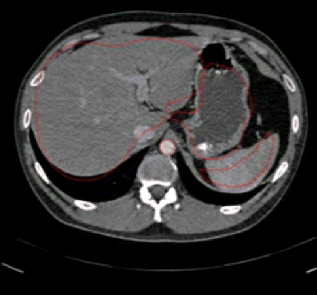

Input image: